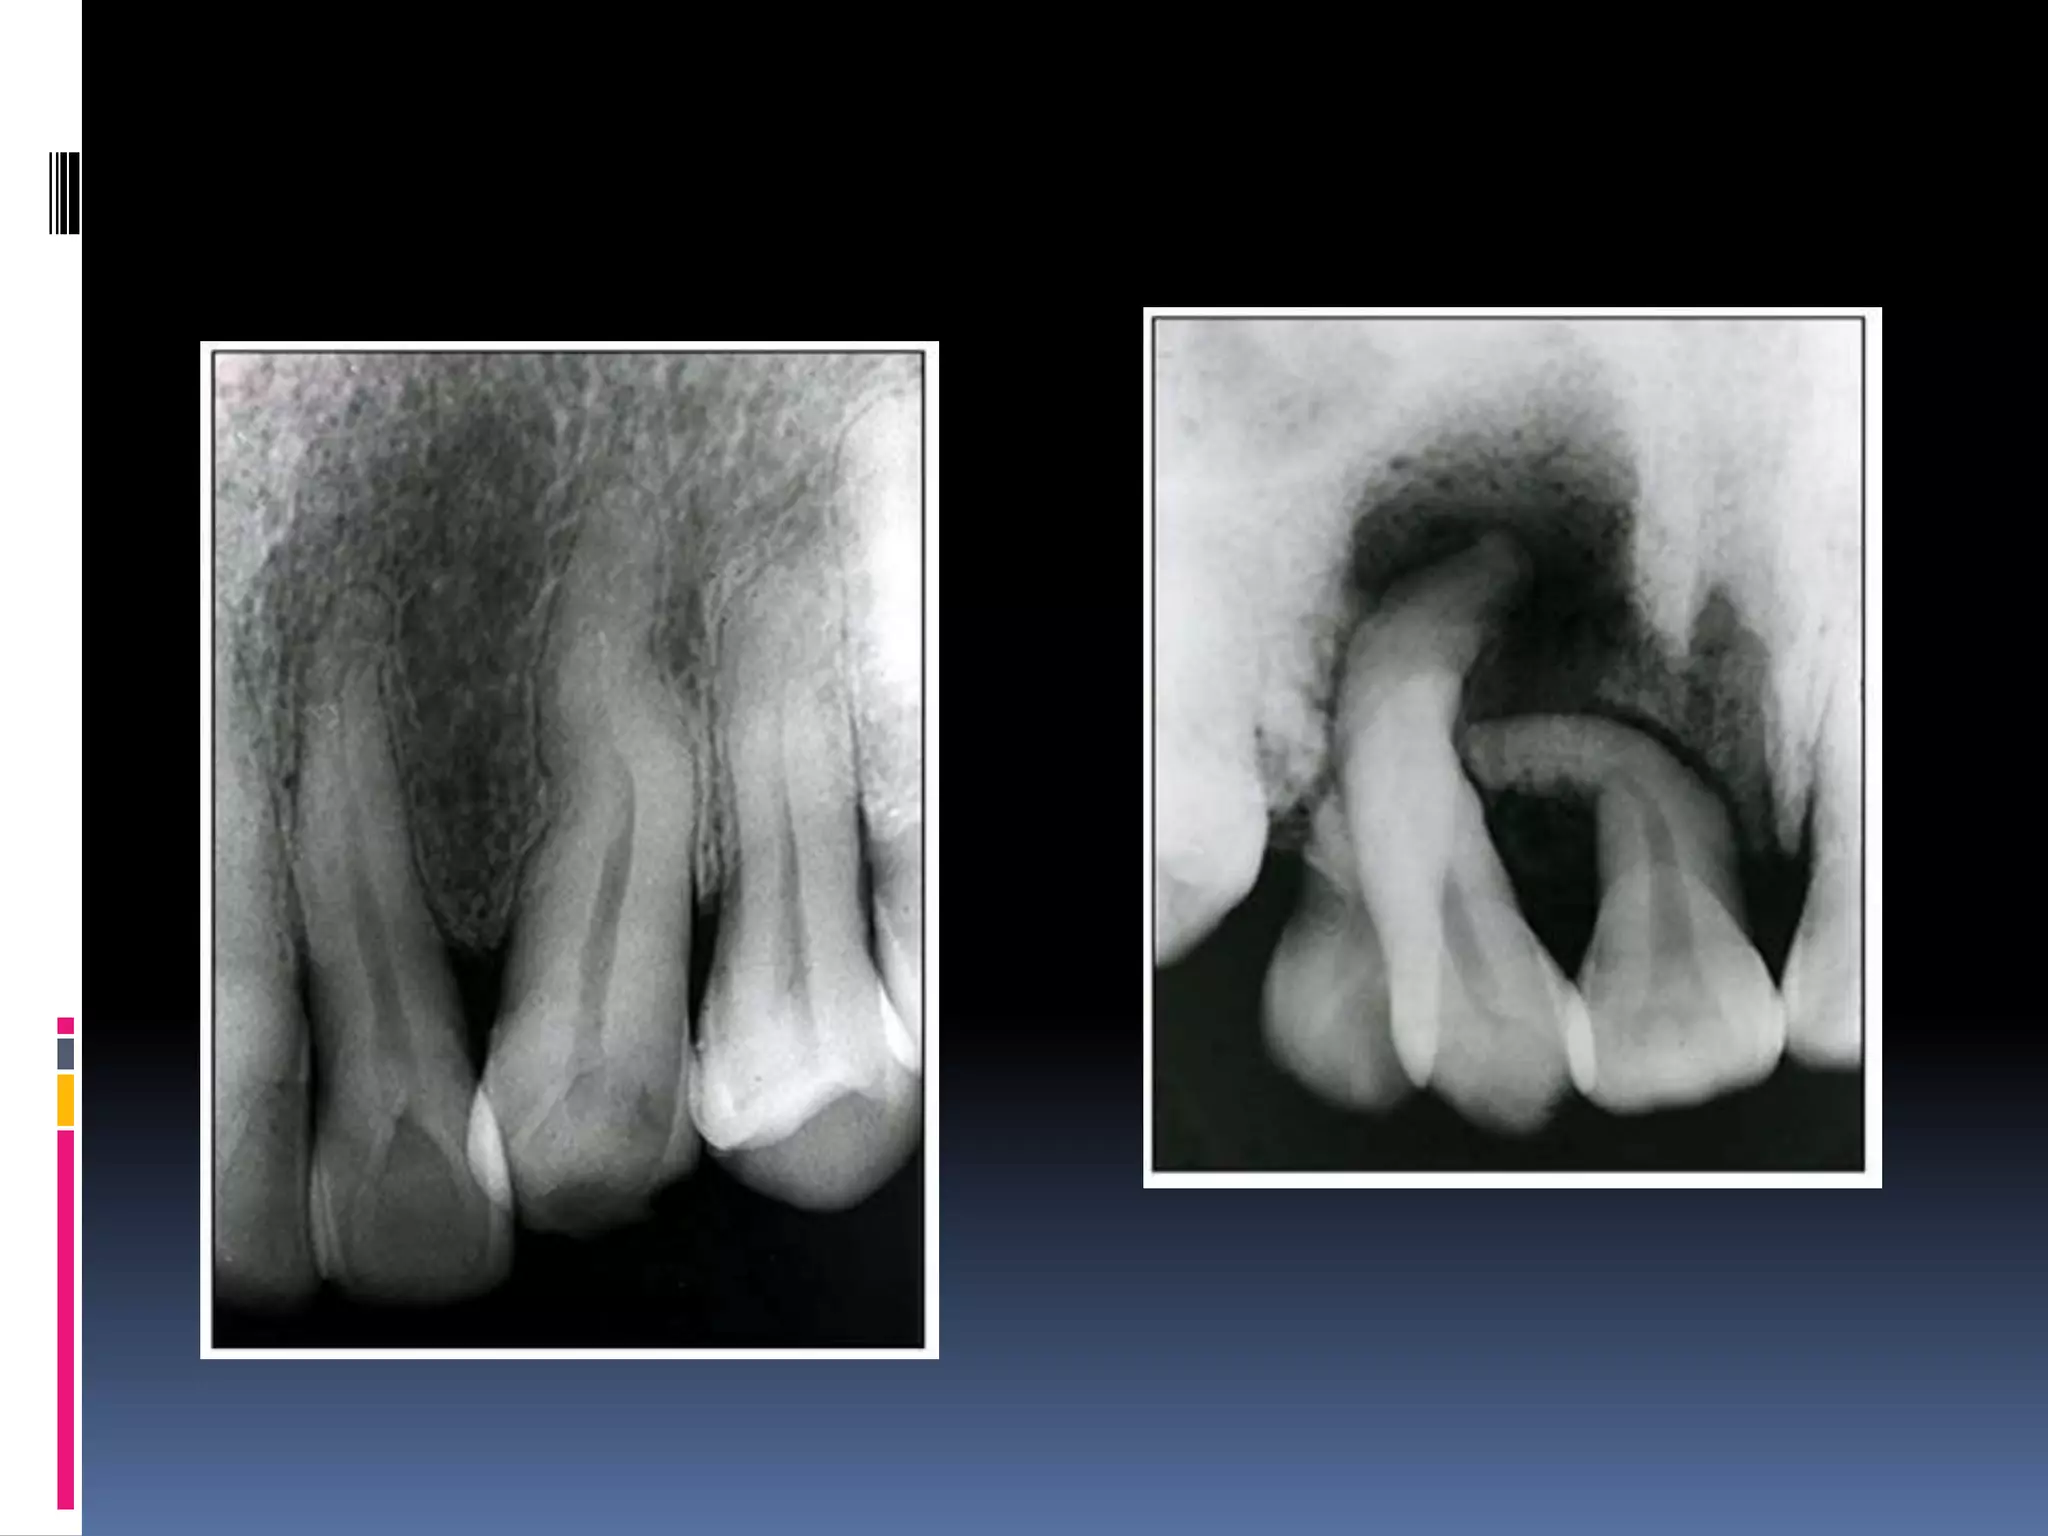

 i) dilaceration

 Abnormal angulation /bend in root.

 Mostly idiopathic , but can occur due to injury

, due to cyst /tumour.

 Mostly in mad third molar, then max secon